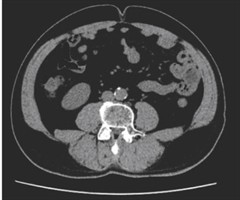

腹部脂肪面积对冠心病的预测价值

摘要目的:探讨基于腹部CT测量腹部脂肪面积对冠心病的预测价值。方法:回顾性收集2021年12月—2024年4月在我院心内科住院的104例病人的临床资料,根据冠状动脉造影结果分为冠心病组(66例)和非冠心病组(38例)。基于腹部CT图像,应用...